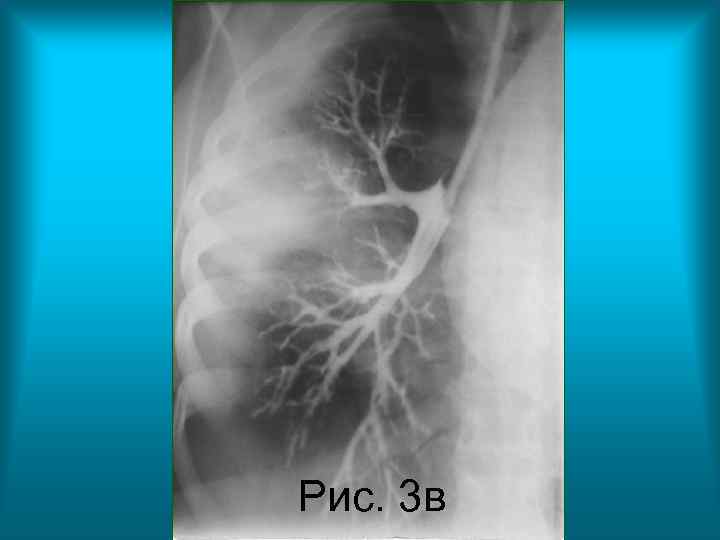

• Рис. 3 в. , Рис. 3 г. Контрастное исследование бронхиального дерева правого легкого в прямой проекции (бронхография). Определяется сужение и неравномерное заполнение контрастным веществом сегментарного и субсегментарных бронхов третьего сегмента верхней доли правого легкого. Бронхи средней доли правого легкого проходимы, веточки их сближены, но не деформированы.

Рис. 3 в Н. С. Воротынцева. С. С. Гольев Рентгенопульмонология